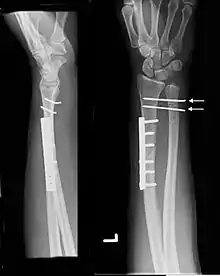

| Galeazzi fracture. Arrow points at the dislocated ulnar head |

شکستگی گالیوزی - (به انگلیسی: Galeazzi fracture) شکستگی دیاستال سوم زند بالایی با جابجایی مفصل رباط دیستال میباشد. یک شکستگی متداول شامل شکستگی و جدا شدن از ناحیه اتصال دومی سوم و سومین شعاع همراه با سوزش یا جابجایی مفصل رشته متصل به رادیولننال میباشد. آسیب در محل مفصل ساعد میباشد.[1]